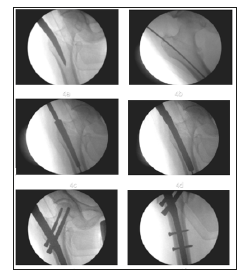

k) Closure: The surgical closure was done in layers and the sterile dressing applied over wound and compression bandage were given (Figure 4).

Figure 4:Surgical technique of PFN insertion – 4a) Nail entry point, 4b) Insertion of guide pin, 4c) Proximal reamer, 4d) Insertion of PFN, 4e) Placement of 6mm anti-rotation and 8mm compression screws and 4f) Placement of 4.9 mm distal cortical screws.